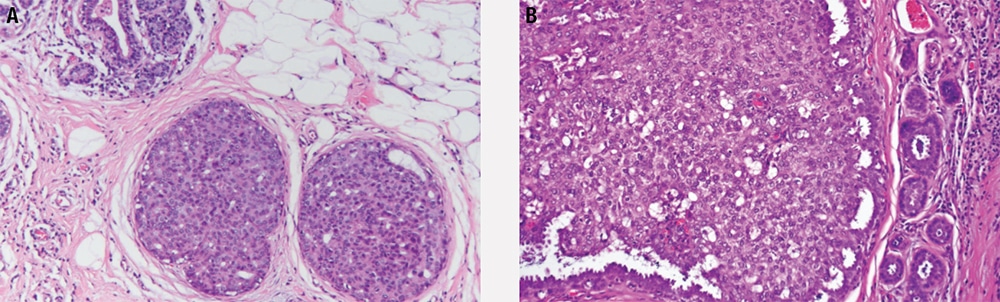

- ADH is an intraductal proliferation (Figure 5-9) in which the qualitative morphologic features of low-grade DCIS are present focally.

- Distended lobules (Figure 5-10) are seen filled with loosely cohesive, monomorphic cells with low-grade nuclei.

- The lobule is expanded (Figure 5-11), and acini are filled with small, loosely cohesive monomorphic cells (classic type), by definition in greater than 50% of a terminal duct lobular unit.

- DCIS can be low, intermediate, or high grade (Figure 5-12). Grading is based largely upon nuclear features, but some grading systems take necrosis into account.